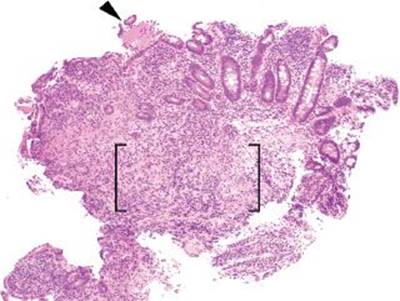

Figure 3.55 Acute ileitis pattern, prominent ulceration. Acute ileitis refers to a fairly wide range of mucosal injury patterns ranging from scattered neutrophils in the epithelium to deep penetrating ulcerations and fissures. In this example, a prominent ulceration is featured (arrowhead), while the background mucosa is essentially unremarkable at this power. The terminal ileum findings were attributed to the established history of excessive NSAID usage.

Medication-related injury constitutes the most common cause of the acute ileitis pattern of injury, particularly in adults. In an endoscopic study of long-term NSAID users, up to 71% showed distal small bowel mucosal injury compared to only 10% of non-NSAID users (p < 0.001).8 NSAIDs mediate injury via nonselective inhibition of cyclooxygenase isoenzymes resulting in decreased production of mucosal protectant products, such as prostaglandins, mucin, and bicarbonate, and dampened microcirculation. The injury pattern can range from mild acute ileitis to erosions, deep-penetrating ulcerations, perforations, and necrosis (Fig. 3.55). The so-called diaphragm disease is a rare but clinically significant consequence seen in up to 2% of patients with chronic NSAID usage and is presumed to be pathognomonic for NSAID-related injury. See also Diaphragm Disease, Chronic Ileitis, this chapter. Although NSAID-related injury can occur at any point along the tubular GI tract, the terminal ileum is particularly vulnerable because of the increased popularity of extended release formulations that delay release of NSAIDs (and the associated mucosal damage) from the stomach to distal bowel segments, including the terminal ileum9 and even the colon.10,11 Other proposed factors include the geographic specific constraints of the terminal ileum; the prominent lymphoid aggregates and narrowed ileocecal valve may result in increased tablet-mucosal contact and related physical and or chemical injury.9